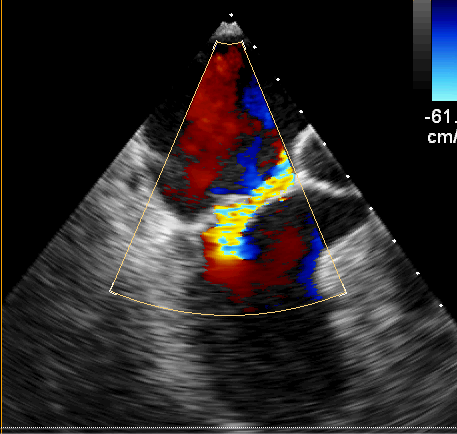

术前超声

经过积极完善术前检查,心脏超声提示二尖瓣后叶脱垂(P2区),偏心反流(3+—4+级),三尖瓣少量反流,目前最严重的就是二尖瓣这扇“门”,如果不及时处理,患者很快就会出现心衰,甚至危及生命,考虑患者高龄,同时不愿接受人工瓣膜置换,高峰主任团队经过缜密研究和充分评估,认为患者有微创手术瓣膜成形的条件,可以通过该术式解决这个大难题。相较于瓣膜置换术,瓣膜成形对主刀医生在术中的精细操作与精准判断提出更高的要求。而微创手术,减少了术中的牵拉和损伤,术后胸骨完整性得以保留,具有创伤小、出血少、恢复快,对术后美观和呼吸功能具有显著优势。在兄弟科室的密切配合下,仅用3个多小时,高峰主任团队通过右侧肋间一个5厘米的小口子,成功对损坏的二尖瓣进行了修复重建,心脏复跳后复查心脏超声,二尖瓣微量返流,手术效果满意。患者安返心外科监护室,在医护人员的精心照护下,患者恢复良好,第二日转回普通病房进一步康复治疗。